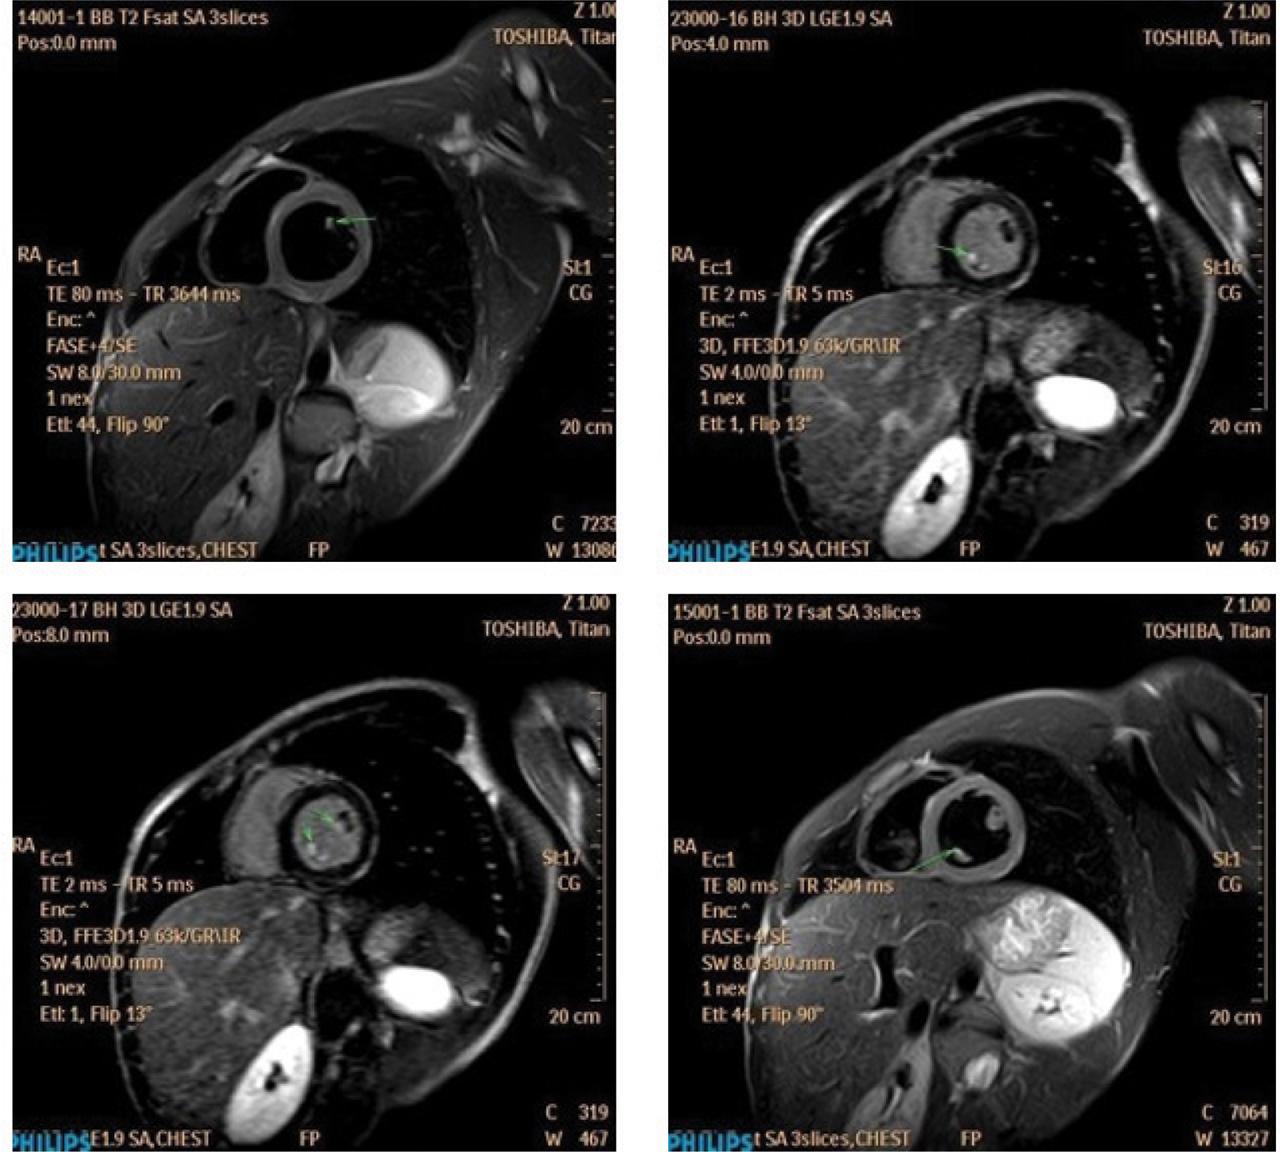

Figure 2